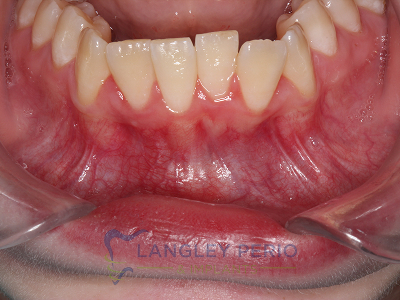

Case 1

Connective tissue grafting was performed to correct gingival clefting caused by over-aggressive toothbrushing